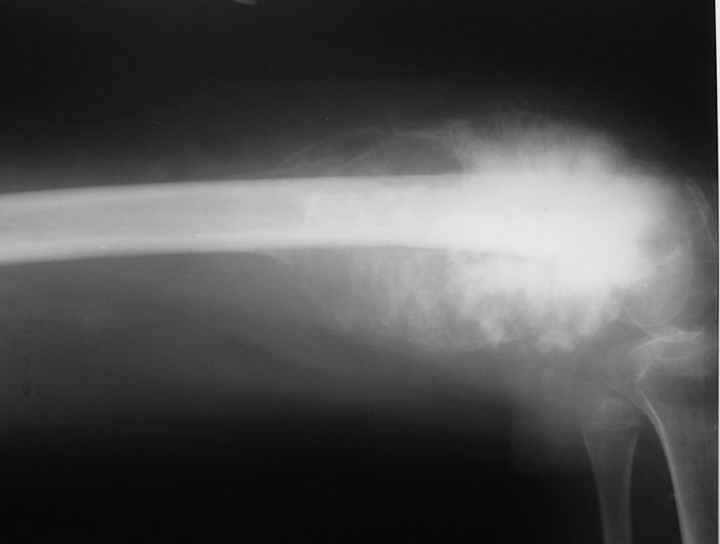

Запущенная опухоль

Девочка 14 лет. Остеогенная саркома бедренной кости. Множественные метастазы в лёгких.Долго лечили от разных форм артрита в одном из городов Татарстана.Ленар Рашитов